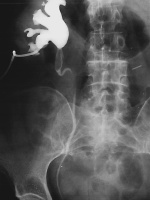

Harnwegsinfekte: Was macht der Urologe und wann sollte er eingeschaltet werden?

Journal für Urologie und Urogynäkologie 2011; 18 (1) (Ausgabe für Schweiz): 32-34 Journal für Urologie und Urogynäkologie 2011; 18 (1) (Ausgabe für Österreich): 31-32 Volltext (PDF) Abbildungen